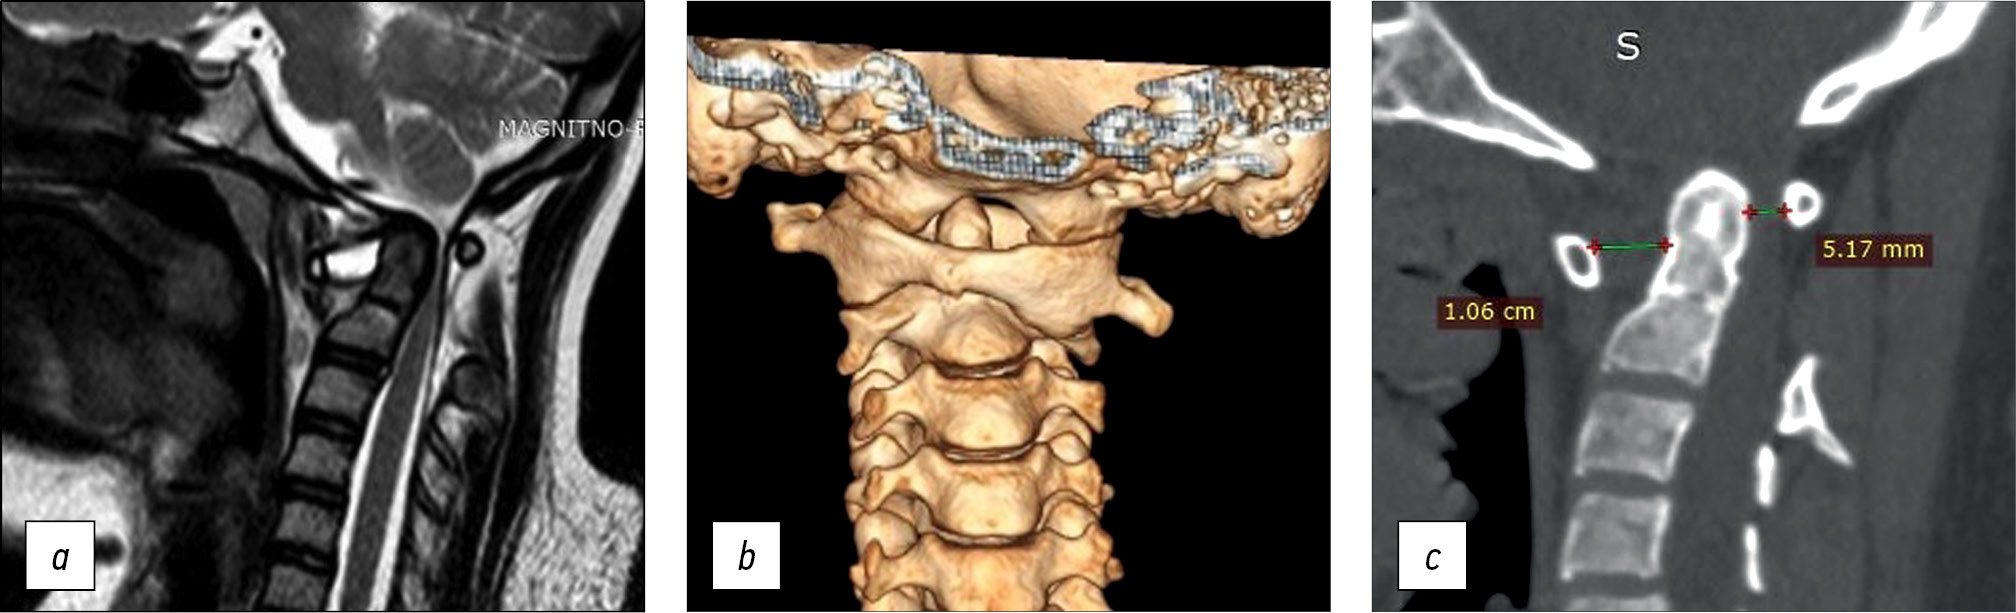

The subluxation of the C1 vertebra was fully repaired with restoration of all craniovertebral ratios: the ADI and SAC were 2.82 mm and 1.72 cm, respectively. The spinal canal stenosis at the C1–C2 level was eliminated, and the fixation elements were appropriately implanted (Fig. 6).

Fig. 6. Рostoperative radiology examination: a — CT sagittal slice, b — 3D reconstruction of cervical CT, c — MRI sagittal slice with elimination of spinal canal stenosis and residual myelopathy. CT — computed tomography, MRI — magnetic resonance imaging.